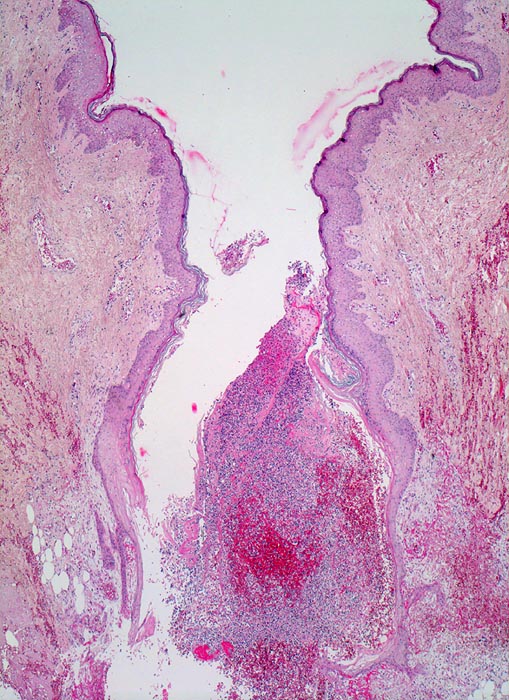

Wundheilung

Entzündung / Reparatur

Haut, Rumpf

Spaltförmiger Defekt des Plattenepithels, der sich fortsetzt in die darunterliegende Cutis. Der Spalt ist angefüllt mit Blut, Fibrin, Detritus (vorläufiger Propf). In den obersten Schichten massenhaft neutrophile Lenkozyten.

6 Tage alte Wunde am Abdomen nach Laparotomie.

Noch keine wesentliche Pflasterepithel-Regeneration möglicherweise als Ausdruck einer Wundheilungsstörung.

Histologie

25